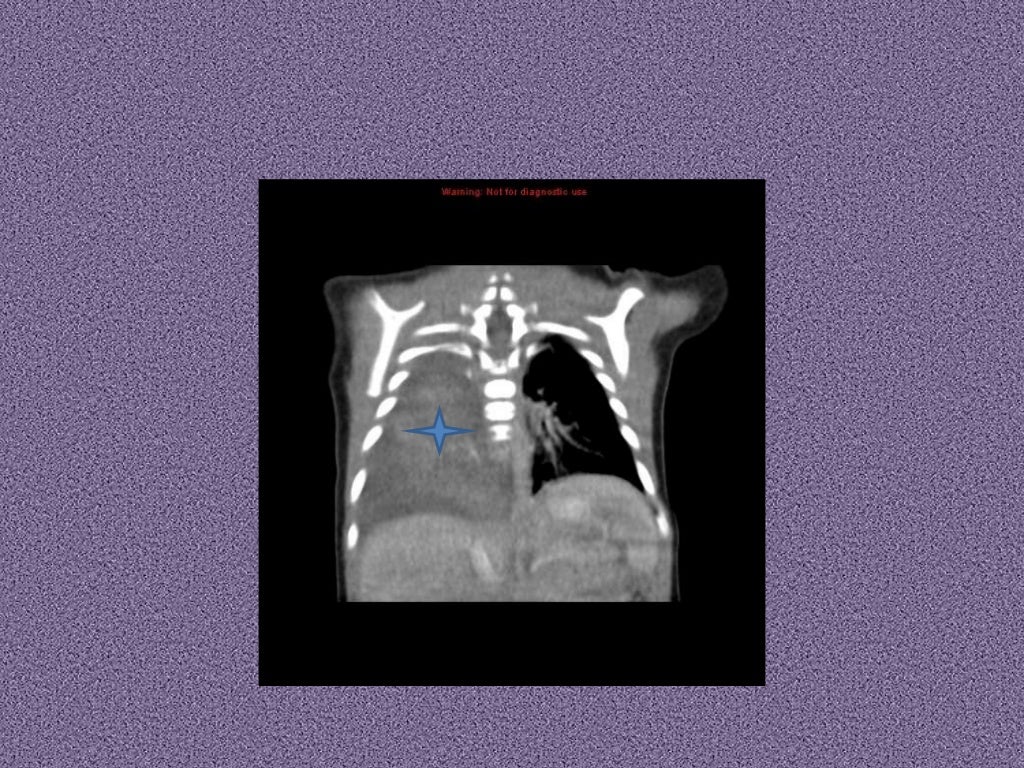

From www.researchgate.net

An 8monthold girl presented with recurrent chest infections since 4 Child Chest Infection Nice Examine the child's chest, and record their respiratory rate, pulse, and blood pressure. All nice products on respiratory infections. Measure the child's oxygen saturation in room. Covers the management of children presenting with wheeze in association with a respiratory. For general advice to give to children and their parents, or carers, see antibacterials, principles of therapy. This guideline sets out. Child Chest Infection Nice.

From www.semanticscholar.org

Figure 1 from Case report of idiopathic pulmonary haemosiderosis in a Child Chest Infection Nice All nice products on respiratory infections. Seek specialist advice, or refer. An upper respiratory tract infection should be considered in a child with a cough, symptoms and signs of infection, and a clear chest on. Includes any guidance, advice and quality standards. Examine the child's chest, and record their respiratory rate, pulse, and blood pressure. For general advice to give. Child Chest Infection Nice.